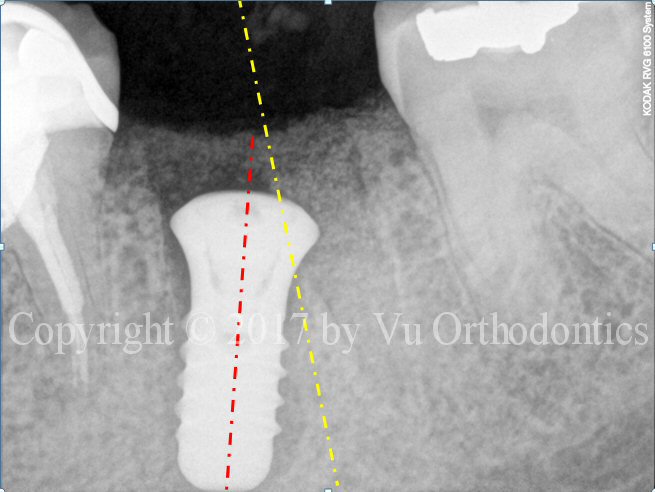

A case of bad implant placement (which was done elsewhere) is shown in Fig. 1. In this case, the implant was placed not parallel to the adjacent roots. Its axis should be along the yellow line -- not the red one. It was also placed too deep. More importantly, the implant is of the wrong type. It is a tissue-level implant (of Straumann), so the top part of the implant should be above the bone level -- should not be below the bone level, as shown.

Fig. 1. Bad implant placement: the axis is supposed to follow the yellow line, not the red one.